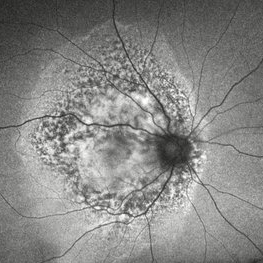

Fractal Pattern of Chronic Serpiginous Choroiditis Fractal Pattern of Chronic Serpiginous ChoroiditisJun 17 2025 by Guilherme Sturzeneker, MD, MSc Ultra-widefield fundus photograph and autofluorescence of a 33-year-old woman with longstanding serpiginous choroiditis in the right eye. The image reveals centrifugal chorioretinal atrophy forming a dramatic fractal-like pattern, sparing the fovea. The patient is several years post-onset, with repeated negative workups, including for tuberculosis. Despite extensive lesions, the patient retains 20/20 vision in both eyes. Management included azathioprine monotherapy, as systemic steroids were contraindicated due to bipolar disorder. Photographer: Andrea Almeida, IPEPO - Instituto da Visão Imaging device: Optos Silverstone Condition/keywords: autoimmune uveitis, azathioprine, chorioretinal atrophy, serpiginous choroiditis, ultra-wide field imaging